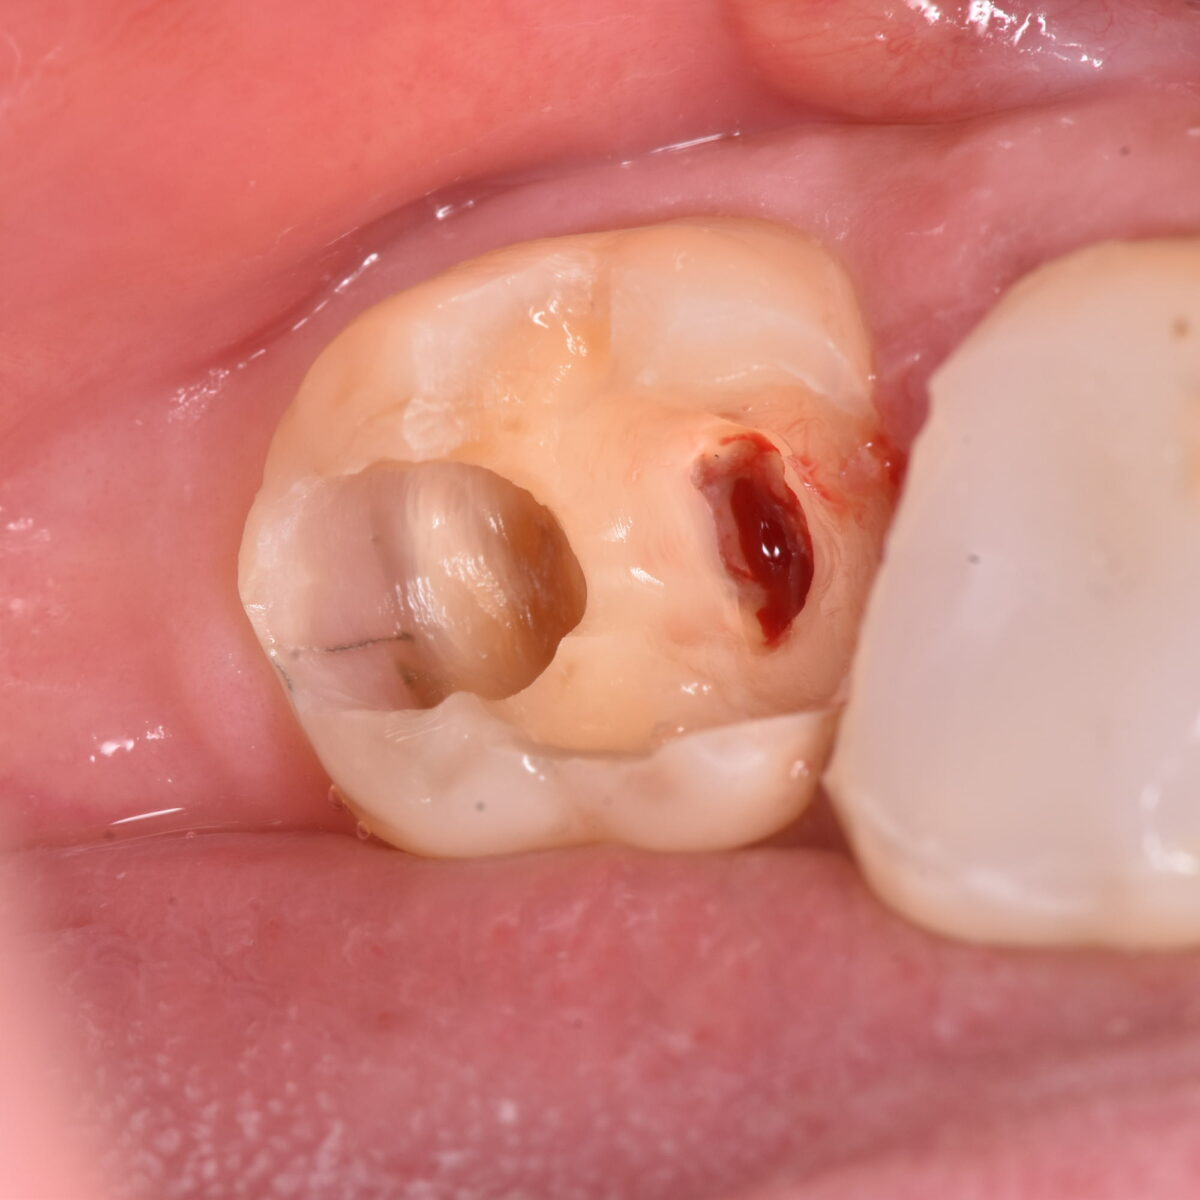

むし歯の広がりは、削ってみないとわからない。歯の神経近くまで広がっていることもある

小さなむし歯だからといって、安心できるわけではない 【東京メトロ東西線妙典駅 徒歩5分の歯医者】市川、妙典の歯科医院、めぐりデンタルクリニックの梶原です。 以前にも、似たような内容…

外側から一目でむし歯の大きさがわかるわけではないことを教えてくれるケース

歯の状態を見て、むし歯の大きさはわかるのか? 【東京メトロ東西線妙典駅 徒歩5分の歯医者】市川、妙典の歯科医院、めぐりデンタルクリニックの梶原です。 むし歯の状態は目で見てわかるの…